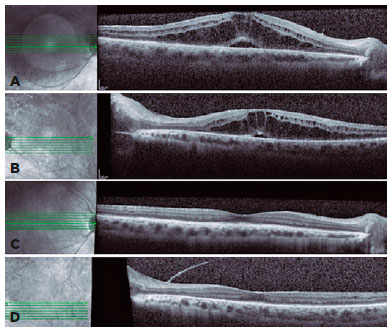

Ophthalmic evaluation revealed visual acuity of counting fingers, biomicroscopy with 4+ anterior chamber cells, 3+ flare, posterior synechiae, and no keratic precipitates in OU. Intraocular pressure was normal, and fundoscopy was difficult to perform due to posterior synechiae and media opacity. As the abnormalities were noted, and the suspicion of severe panuveitis was considered, we promptly initiated treatment with topical dexamethasone (1 mg/mL every 2 hours) and tropicamide (1 mg/mL every 8 hours) with slow withdrawal for 30 days. In addition, the rifabutin dose was adjusted (150 mg/day). After 30 days, anterior chamber inflammation improved (Figure 1). Fundoscopy showed vitreous opacities OU and inferior vasculitis in the left eye. However, the patient’s visual acuity remained low, and an optical coherence tomography revealed macular edema OU (Figures 2A and 2B). After tapering the topical corticosteroid and adjusting the rifabutin, full recovery of panuveitis was achieved after two months (Figures 2C and 2D).